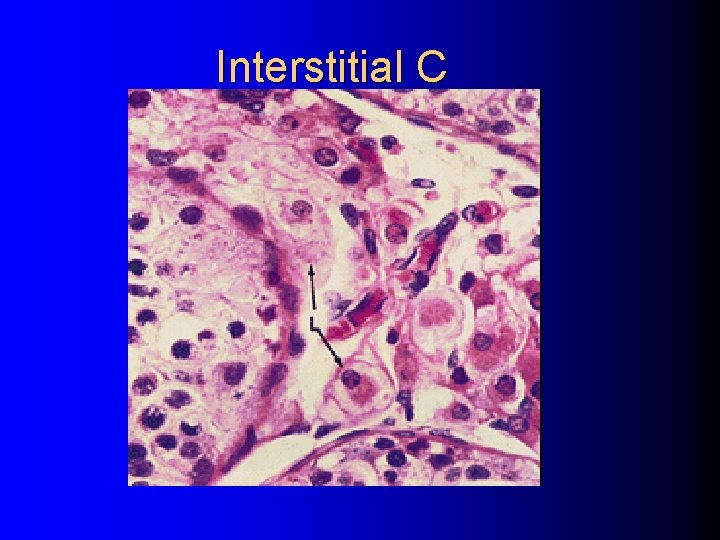

(二)interstitial C l Leydig C, In group, large , polygonal, highly eosinophilic. l Steroid-secreting C: elaborate s. ER, Mit. With cristae. Secret testosterone/androgen

Interstitial C